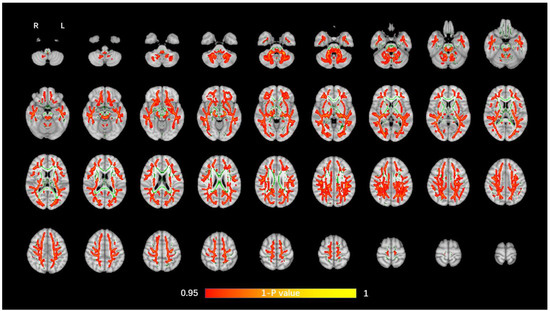

The average FA WM skeleton of all subjects was constructed in TBSS analyses, as shown by the green line in Figure 1, Figure 2, Figure 3 and Figure 4. An analysis of variance of voxel level was carried out on the WM skeleton, and the differences among the three groups were compared. p < 0.05 after FWE correction based on TFCE was statistically significant. Statistically significant areas were expanded to better show the position of WM fiber bundles, as shown in the red part in Figure 1, Figure 2, Figure 3 and Figure 4. The statistical results showed that the DTI indexes of most fiber bundles were statistically significant. There was a significant statistical difference in the FA, MD, AD, and RD values of the FMI, FMA, IFOF, SLF, ILF, ATR and corticospinal tract (CCT) among the three groups (p < 0.05; Figure 1, Figure 2, Figure 3 and Figure 4).

Figure 3.

Voxel-wise TBSS analysis results of AD images among the WML-VCIND, WML-VaD, and HC groups. Green represents the mean WM skeleton of all subjects. Red-yellow (thickened for better visibility) represents regions with a significant F-test statistical difference (p < 0.05, TFCE-based FWE-corrected). TBSS, tract-based spatial statistics; AD, axial diffusivity.